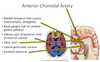

An issue with which artery / vein would cause issues with:

- Medial temporal lobe (uncus, hippocampus, amygdala)

- Basal ganglia (tail of caudate, globus pallidus)

- Inferior part of posterior limb of internal capsule

- Optic tract

- Lateral geniculate nucleus

- Cerebral peduncle

Anterior Choroidal Artery